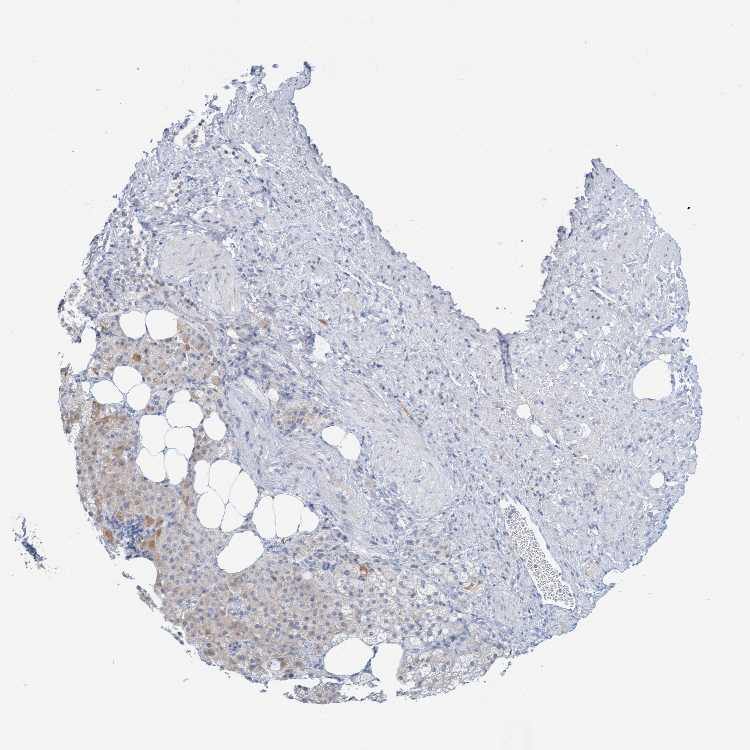

ADRENAL GLAND - Antibody stainingi

Antibody staining in the annotated cell types in the current human tissue is reported as not detected, low, medium, or high, based on conventional immunohistochemistry profiling in selected tissues. This score is based on the combination of the staining intensity and fraction of stained cells.

Each image is clickable and will lead to virtual microscopy that enables deeper exploration of all samples and also displays staining intensity scores, fraction scores and subcellular localization as well as patient and tissue information for each sample.

Antibody HPA006479Antibody HPA008689Antibody CAB020712

Glandular cells MediumLowLow